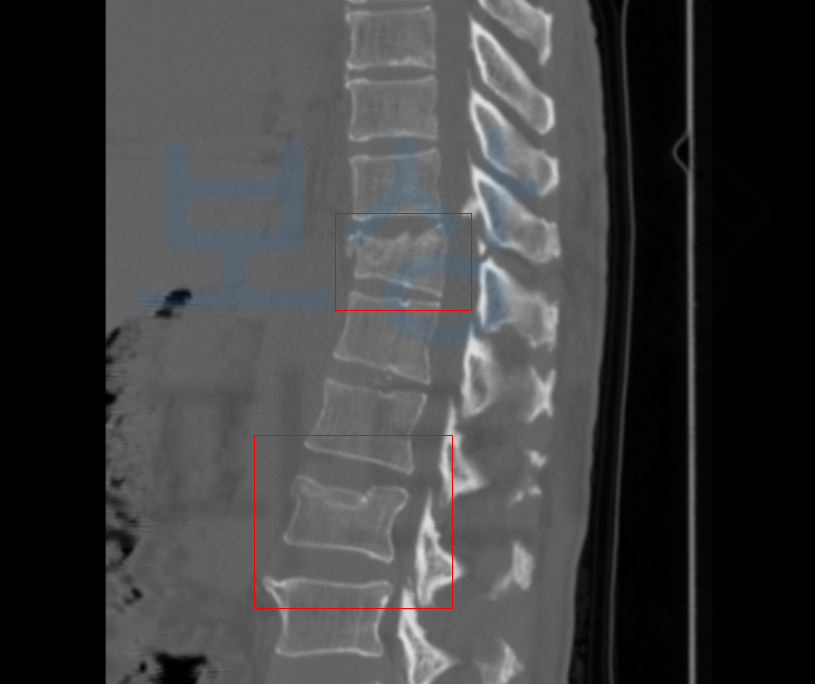

T11, L2 즉 흉추 11번과 요추 2번의

압박골절 진단을 받으셨고 최소 16주간의 요양이 필요했습니다. 하지만 몇 주가 경과했음에도 골절된 척추체는 회복되기 어려웠고 결국 T11에 Kyphoplasty 풍선성형술 L2 는 vertebroplasty 경피적척추성형술 골시멘트술 받게 되었습니다.